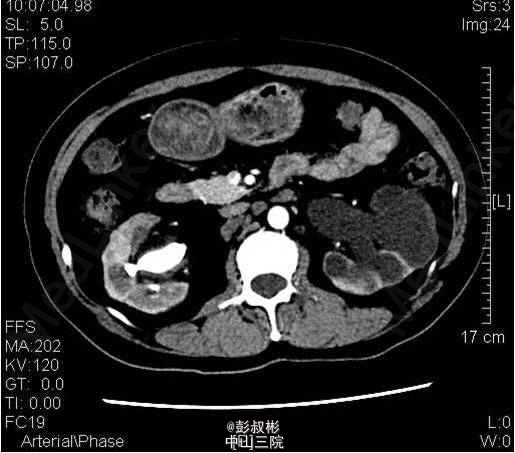

1、因“反复下腰部胀痛伴发热2月,加重10天” 入院。入院前最高体温39.5℃ ,外院检查尿隐血及尿白细胞3+,进一步行泌尿系B超显示双肾及左输尿管下段结石,左肾重度积液 。 2、既往史: 10年前因肾结石行体外冲击波碎石术,自诉术后恢复良好。 3、辅助检查:1) 血常规(抗炎后)、血生化(补钾后)、肝功、凝血、术前八项、胸片及心电图未见明显异常; 2) 尿常规:12.9 :尿液白细胞+++ 尿液红细胞++ 左肾造瘘液白细胞++ 左肾造瘘液红细胞++ 3) 真菌培养:无真菌生长 4) 肾功能:12.9: 肌酐5.68 mmol/L尿素氮: 186 nmol/L 5) 核素肾动态显像+GFR双血浆测定 1.右肾灌注、功能中度受损,右上尿路慢性梗阻。 2.左肾灌注、功能中度受损,左上尿路机械性梗阻。 灌注相:双肾于腹主动脉显影后2秒开始显影,放射性灌注明显减低(右肾明显低于左肾)。灌注曲线分析:双肾灌注峰明显减低。 功能相:右肾影稍增大,放射性摄取明显减低,放射性分布不均匀,可见多发放射性分布稀疏缺损区,放射性排泄缓慢。左肾增大,放射性摄取减低,放射性分布不均匀,可见多发放射性分布稀疏缺损区,放射性排泄缓慢,左肾盏见明显放射性滞留。半小时内膀胱可见放射性积聚。 肾图:右肾a段降低,b、c段融合为低水平延长型肾图。左肾a段降低,b、c段融合为持续上升型肾图。双血浆法肾小球滤过率(GFR)左肾为19.7ml/min,右肾GFR为17.9ml/min。 6) 双肾CTU平扫+增强螺旋扫描 1、左肾多发结石、重度积液、肾功能减退,左输尿管膀胱入口处结石,左侧输尿管炎症; 2、右肾多发结石、轻度积液,右肾功能减退,右肾盂及输尿管炎症。 4、诊断:双肾积脓 右肾铸形结石 左肾多发结石 左输尿管下段结石碎石术后 双肾功能减退 5、入院后处理:予以“舒普深” 3.0 Bid 抗感染,12-5 行“B超引导下经皮左肾穿刺造瘘术”,每日引流出约1500ml脓液。肾功能改善后于12-9行“左侧输尿管镜下钬激光碎石取石术”,术程顺利,术后予以舒普深3.0 Bid抗感染,体温正常。昨日下午行“B超引导下经皮右肾穿刺造瘘术”。